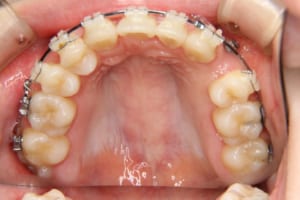

治療中

治療内容 唇側矯正装置を使用した成人矯正治療を行いました。

使用した装置 マルチブラケット装置(唇側矯正)

InVuブラケット

シルバーワイヤー

ホールディングアーチ

歯科矯正用アンカースクリュー(1本)

その他/備考 上顎右側中切歯および側切歯が、埋伏していた犬歯によって歯根吸収していました。

牽引に半年かかりました。